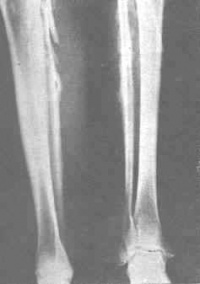

1.慢性氟中毒在成人中主要为不同程度的骨质硬化,晚期可非常明显。骨质硬化可涉及全身,以脊柱、髂骨、骼骨以及肋骨较为常见,也见于四肢长骨。松质骨的增生硬化使骨小梁增粗,继而髓腔缩小以至消失。骨膜增生可使骨边缘不平,并有增大或增粗现象。

3.氟骨症骨骼除有增生硬化外,亦可有骨质疏松、软化、生长障碍线、关节退变等不同的病理改变和X线征象。